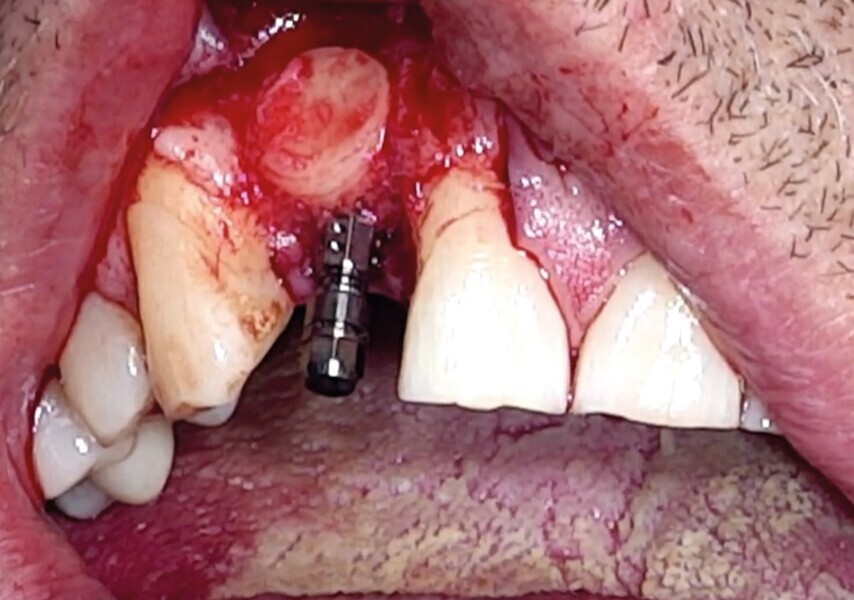

Une fracture radiculaire de 22 a lésé la table osseuse vestibulaire et la gencive en regard. Elle est extraite minutieusement à l’aide du Benex (Fig. 19). Un curetage de l’alvéole est réalisé manuellement puis au contra-angle, à l’aide d’une fraise boule multilame de gros diamètre. Un lambeau de pleine épaisseur est soulevé (Fig. 20).

Comme la technique initiale, le défaut osseux est calibré par un trépan (Fig. 21) d’extraction-implantation immédiate, plus apicale que l’apex de l’alvéole dentaire et aux dépens de la corticale palatine.

Dans certaines situations cliniques, l’étude radiologique tridimensionnelle montre un volume osseux exploitable en position de 18 ou 28. Il est alors aisé de réaliser le prélèvement au trépan, sur ces sites habituellement larges. Toute la pertinence dans ce cas est de le réaliser à travers la gencive kératinisée et obtenir ainsi une carotte ostéo-gingivale (Fig. 22). De ce fait, il ne faut pas faire d’incision ou de lambeau pour ouvrir l’accès au trépan. Le geste devient extrêmement rapide mais nécessite une bonne connaissance anatomique, une excellente analyse de la planification 3D, puis un bon repérage clinique.6

Pour connaître la profondeur de trépanation, il suffit d’enfoncer la sonde parodontale et de mesurer l’épaisseur de gencive sur l’os. En y ajoutant 4 mm, la profondeur finale est obtenue pour avoir suffisamment d’os. Une fois la carotte ostéogingivale prélevée (Figs. 23 et 24), il ne faut pas séparer l’os de la gencive, mais réduire l’épaisseur gingivale en supprimant la partie kératinisée (Fig. 25). Un implant cylindroconique (Straumann BLT 3,3 SLActive Roxolid) est parfaitement ancré (Fig. 26). La carotte d’os et sa gencive toujours adhérente, sont alors impactées transversalement à l’implant (Fig. 27). La partie osseuse spongieuse est au contact de l’implant, pendant que le conjonctif qui y est attaché, est utilisé comme un greffon conjonctif enfoui sous le lambeau vestibulaire.